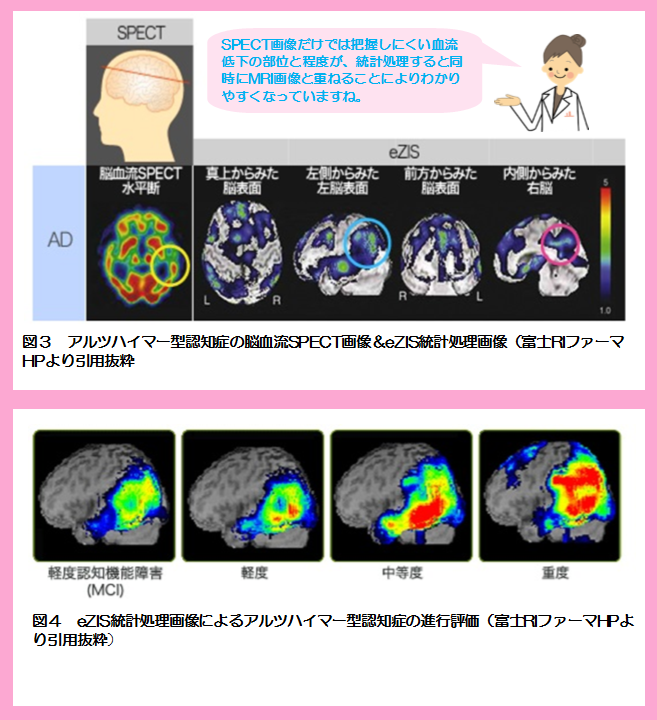

spectの画像

![spect 撮って診る認知症genki55.net|SPECT検査[認知症の進行状況がわかる]](http://genki55.net/img/spect09.gif)